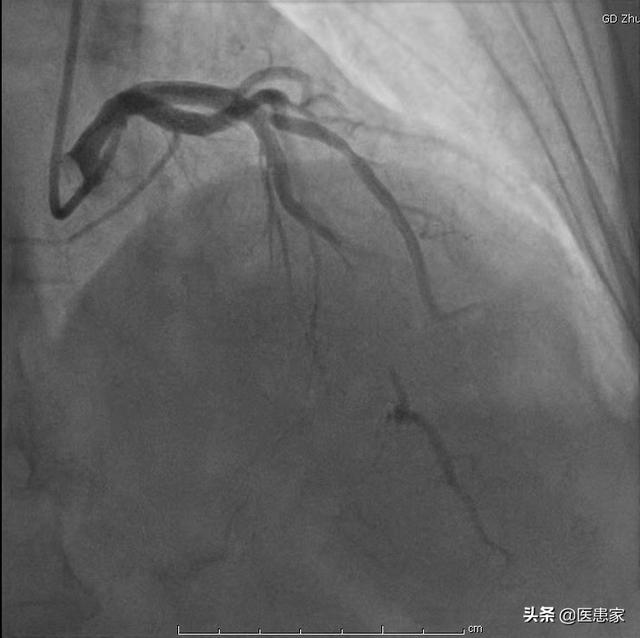

5.冠動脈造影

- 冠動脈造影は検査のために入院が必要で、侵襲的である。

- 冠動脈診断の現在のゴールドスタンダードである、はっきり見えるという利点があり、ある検査で閉塞が非常に深刻であることが判明すれば、再手術の必要なく直接ステントを入れることができる。

- 欠点は、検査費用が高く、入院が必要で、侵襲的であることだ。

チューブを心臓に通して選択的に撮影することで、血管を見たいところを見ることができ、血管がどの程度詰まっているかもわかります。

6.冠動脈造影冠動脈造影は侵襲的な検査であり、現在でも冠動脈疾患診断の "ゴールドスタンダード "である。.狭窄病変の位置を特定し,その範囲を推定することができる。内腔径が70~75%以上縮小すると血液供給に重大な影響を及ぼすことが一般に認められている。

3、冠動脈造影:もし冠動脈CTAが冠動脈性心臓病の診断の銀の標準であるならば、冠動脈造影を金の標準と呼び、誰の意見もあってはならない、冠動脈性心臓病の診断を確認する最も正確な検査であり、誰もない。

1、冠動脈造影

これは冠動脈疾患を判定するためのゴールドスタンダードであり、冠動脈疾患の診断を確定し、その程度を明らかにするために用いられる。利点は、冠動脈が開いているか、プラークや狭窄があるかどうかを医師が目視で観察できることです。また、状況に応じて、適時にステント治療を行うことができます。